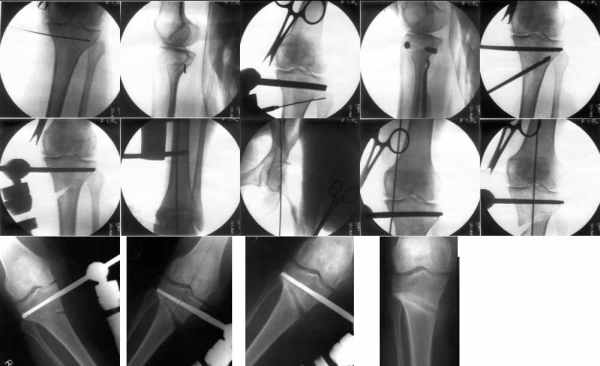

Sending you pics of the steps of the osteotomy and the frame.

You can do the osteotomy in a "focal dome" or in a transverse fashion. The dome has the advantage of having a good contact, allowing weight bearing as tolerated early on.

The level is below the tibial tuberosity.

The frame I use is pretty simple, with one wire each in the proximal and distal ring, two schanz pins in the proximal ring, and one each in the middle and distal ring.

I preconstruct a frame with the proximal ring in varus by the use of coupled washers in the threaded rods in the front and back. These are used as hinges, and after the correction, a medial and lateral threaded rod is also added.

Since the center of rotation of these deformities is usually near the knee joint line, lateral translation of the distal fragment is necessary to normalise all the axes.

You can also do the osteotomy in a transverse fashion.

When I use an orthofix fixator, the osteotomy is oblique, starting below the tuberosity and ending 1 cm away from the lateral cortex at the level of the head of the fibula. No fibular osteotomy is needed there. The deformity is gradually corrected over 2 or three weeks.